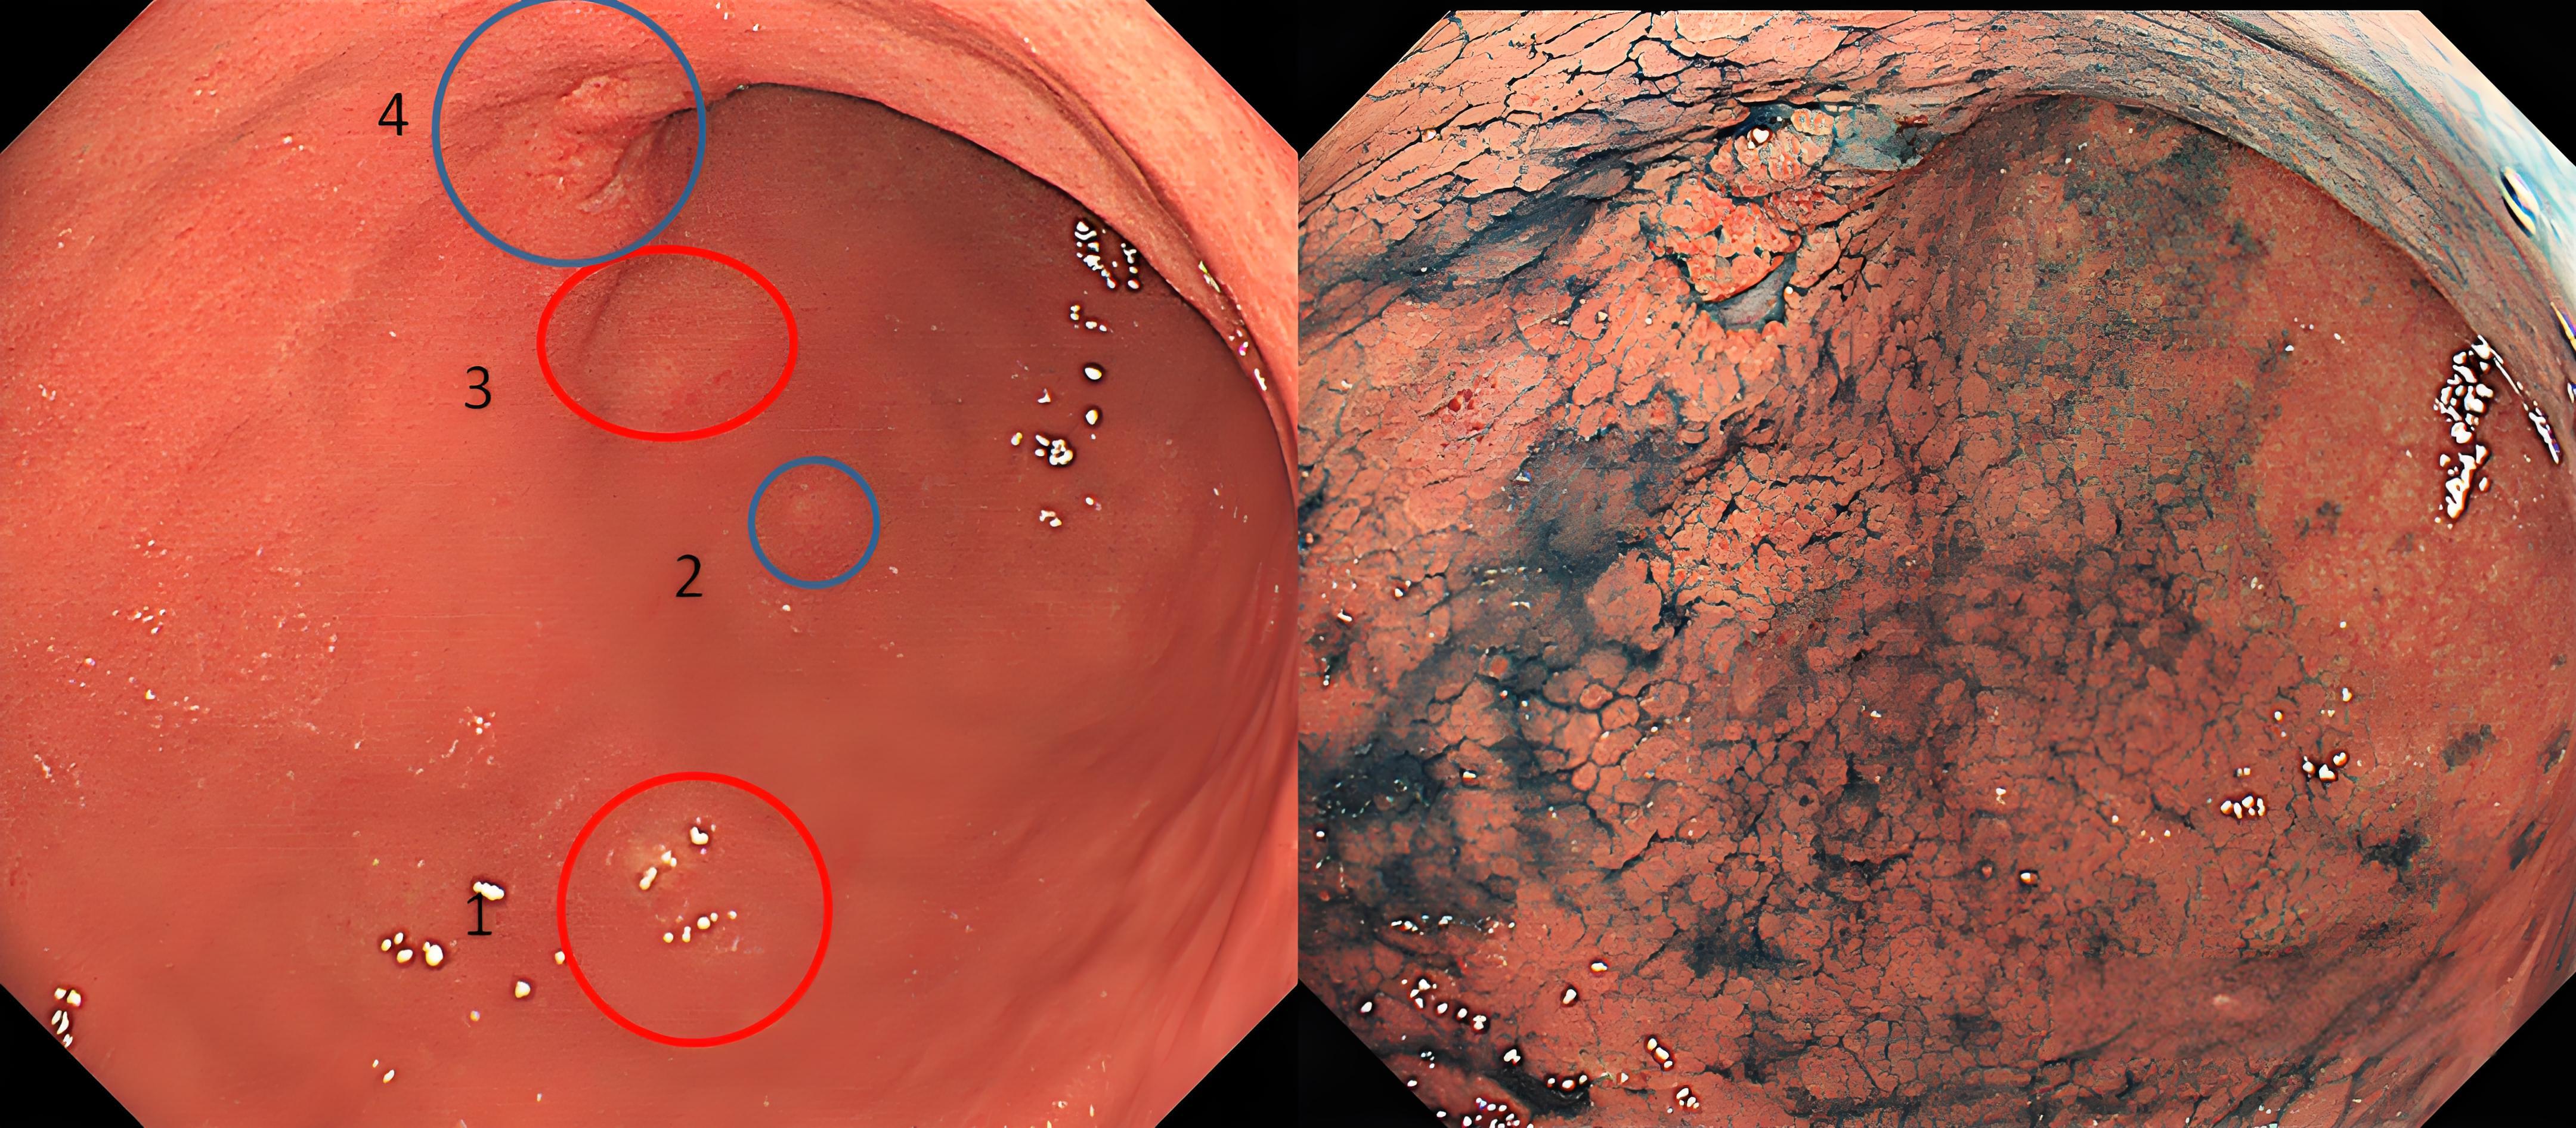

胃镜检查是诊断的第一步,也是关键一步。在胃镜下,胃MALT淋巴瘤可表现为胃黏膜红斑、糜烂和溃疡等。医生会在可疑区域采集组织样本进行活检,这是确诊的依据。

病理检查是诊断的金标准。显微镜下,肿瘤细胞会呈现特征性的"边缘区细胞"增生,并可能形成"淋巴上皮病变"(即淋巴细胞浸润并破坏胃腺体)。